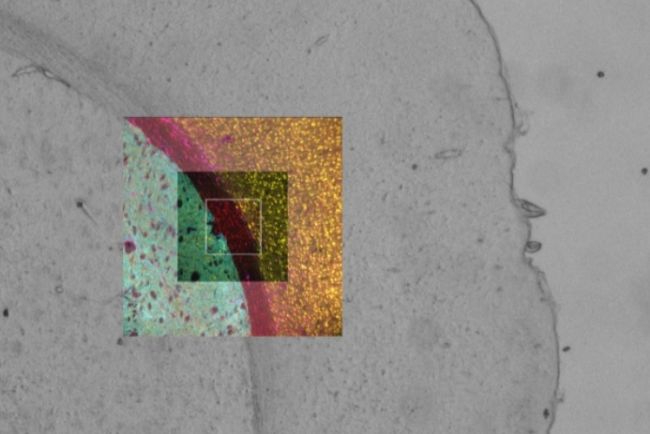

多种载体类型的 Sample Finder 设置。使用 1.6 倍物镜进行盖玻片检测和概览图像采集。

从样本概览图像轻松切换到多通道视图模式,从而在整个工作流程中提供数据的空间情境。

可以观察多通道叠加的图像,并在多通道图像与 Navigator 界面之间切换。

在配备 Quantum 载物台的 DMi8 显微镜上使用 19 毫米和 22 毫米视场的相机对小鼠大脑进行双通道扫描,结果显示后者的扫描速度快了 30%。